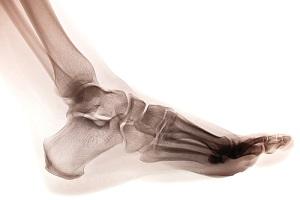

According to court records, the injured had parked the dump truck he was driving in a Farmington cul-de-sac in connection with a landscaping job for which he was partially responsible. The owner of the landscaping business, who was driving a pickup truck and towing a Bobcat on a trailer, pulled up extremely close behind the dump truck, reportedly to "chastise" the dump truck driver for how he had parked. When the owner finished, he went to drive away, and the 4-ton trailer drove over the dump truck driver’s right foot, causing a crush fracture. Surgery was not performed, but the accident allegedly also caused irreversible nerve damage and significant pain.